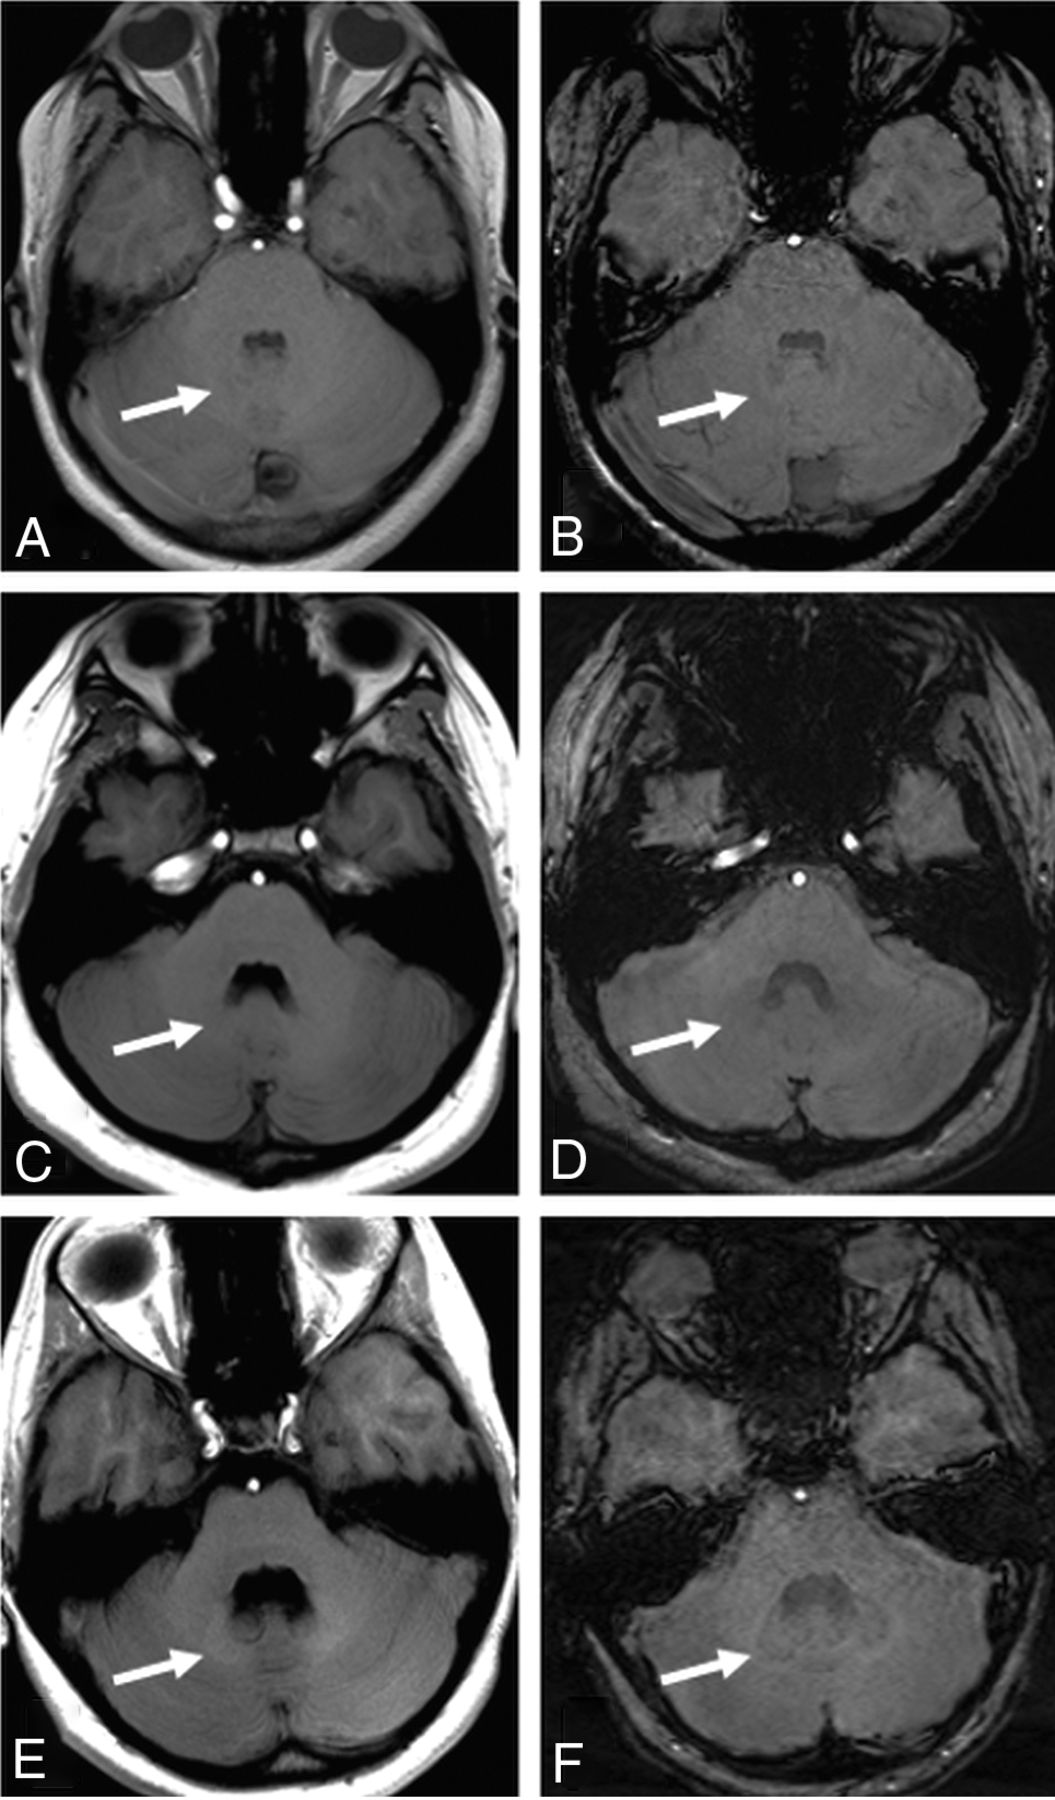

Figure 4 demonstrates representative MR images. Figures 5 and 6 reveal scatterplots of the correlation between the DN-to-MCP ratios on unenhanced T1WI and SWI.

A 13-year-old male patient without gadolinium exposure (A and B), an age- and sex-matched patient after 5 doses of macrocyclic GBCA (C and D), and another 13-year-old adolescent boy after 7 doses of linear GBCA administration (E and F). Note the brighter signal in the DN on T1WI (E) and lower signal in the DN on SWI (F), which is not present in the other 2 children. (White arrows represent DN)